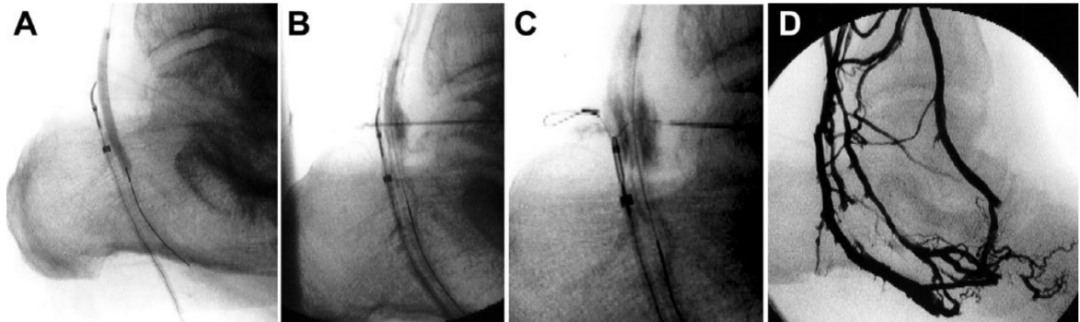

②若静脉位于动脉后方:将针头插入,使其指向球囊(作为动脉位置的标志),并穿过球囊的两壁。一旦针头离开动脉,便进一步向圈套器环的中心推进,直至其完全刺穿通过圈套器环的静脉。收紧圈套器环以确认针头已穿过,将0.018英寸的导丝推进。撤出针头,回撤圈套器环,以便抓住导丝并通过静脉通路引出体外。轻轻撤出刺穿的球囊导管,并在静脉鞘管中引入一根4F支撑导管,然后沿静脉中的导丝将其推进至动脉。最后,将第二根0.014英寸导丝引入导管并推进,直至其明确位于动脉腔内。同样,通过注入造影剂来确认血管通路。然后,完全撤出第一根导丝和动脉球囊导管,并通过4F静脉鞘管扩张动静脉吻合口(见图5和图6)。

图5. 静脉动脉化简化技术 。(A)将针插入,指向动脉球囊导管。(B)针进一步推进,穿过球囊导管,最后在穿过圈套器环时穿透静脉。(C)拔出针;回撤圈套器,通过静脉鞘取回。(D)支撑导管从静脉进入动脉。(E)再放置一根0.014英寸导丝,直到它清楚地定位在静脉腔内。(F)动静脉吻合口血管成形术。

图6. 静脉动脉化简化技术术中造影(A) 静脉圈套器位于动脉球囊导管后方。(B) 22-G微穿刺针经皮推进,穿过球囊和圈套器环。(C) 推进导丝。圈套器环闭合并收回。(D) 静脉动脉化的血管造影图像。